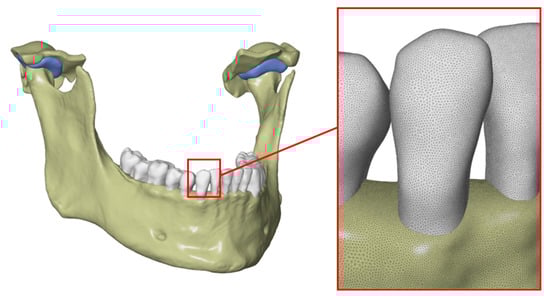

- Creation of an accurate model of the mandible together with the temporomandibular joint. The main assumption was to create a model that could be used for numerical analyses of various clinical cases, allowing the simulation of the work of fixing elements, assessment of the strength and durability of the fixation, and at the same time, without unnecessary simplifications, reflect real human anatomy. The input data were DICOM images obtained from medical imaging using computed tomography. Obtaining three-dimensional models of individual anatomical structures required the segmentation of tomographic images and then edition of the generated surface objects. Reverse engineering software for free modeling and a CAD program for parametric modeling were used.

2.4. Preparation of a Solid CAD Model

2.5. Preparation of an FEM Model